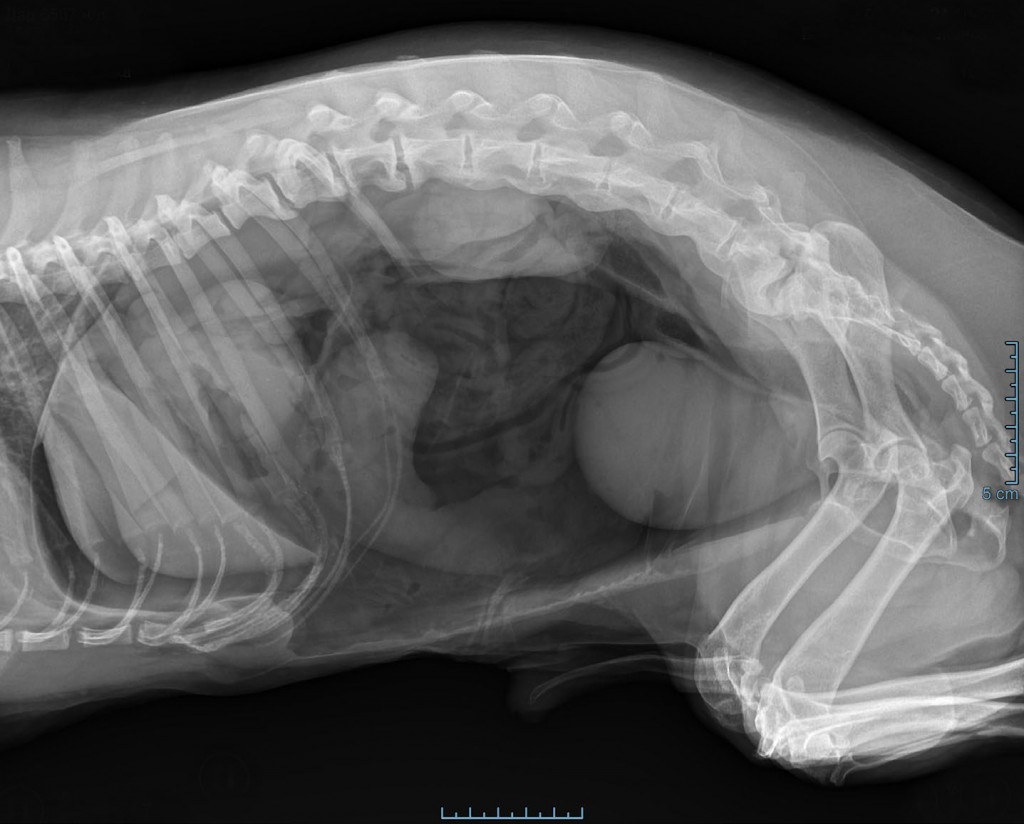

Эндоскопическое исследование показано при подозрении на инородное тело в пищеводе или желудке, для оценки изменений слизистой, в случаях наличия воспаления, рефлюкса, хиатальной грыжи, аномалии сосудистого кольца, неоплазии6. Однако если есть явное подозрение на перфорацию желудочно-кишечного тракта, эндоскопию лучше не проводить, поскольку нагнетанием воздуха во время проведения процедуры можно спровоцировать развитие напряженного пневмоторакса при перфорации пищевода или чрезмерное скопление газа в брюшной полости6 (фото 1).